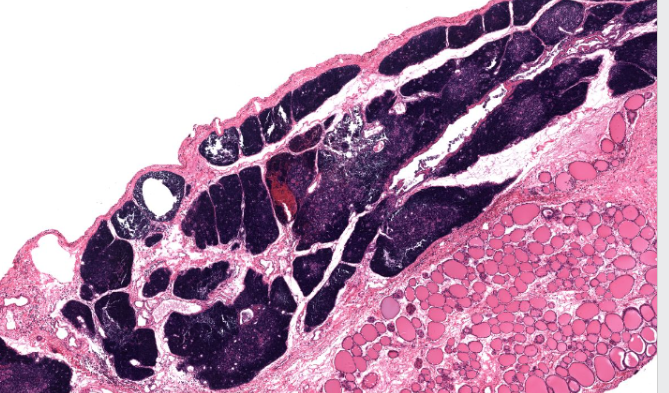

spleen

solid organ

“white” pulp

made up of lymphocytes

lots of basophils

“red” pulp

filters and degrades RBCs